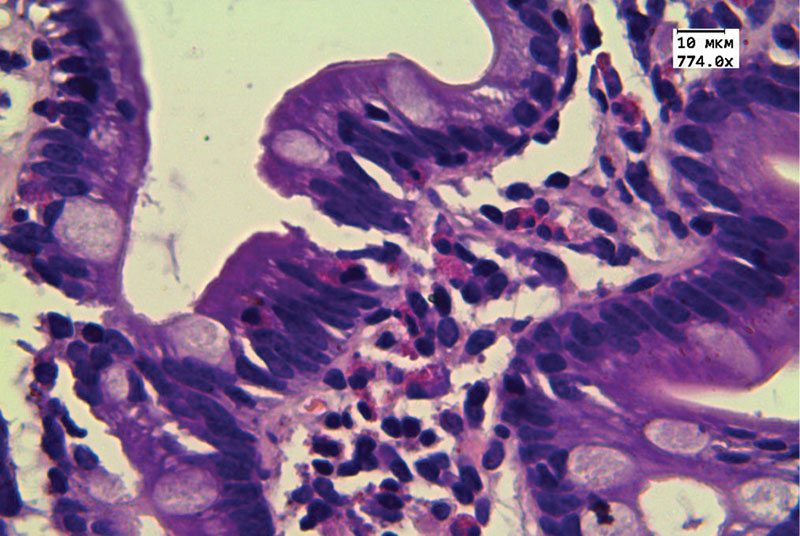

Рис. 3. Гистологическое исследование биоптатов ДПК: инфильтрация эозинофилами эпителия ворсин (превышает 70 в поле зрения при увеличении × 774,0). Окраска гематоксилином и эозином

Гистологическое исследование биоптатов двенадцатиперстной кишки (ДПК) показало отек и диффузную инфильтрацию собственной пластинки лимфоцитами, плазмоцитами, эозинофилами; эозинофилы формировали очаговые скопления, инфильтрировали поверхностный и криптальный эпителий, эпителий бруннеровых желез, мышечную пластинку слизистой оболочки. Эозинофилы находились в состоянии дегрануляции (рис. 1–3).

В биоптатах терминального отдела подвздошной кишки также отмечена эозинофильная инфильтрация, эозинофилы инфильтрировали поверхностный эпителий и эпителий крипт, также отмечена дегрануляция эозинофилов. Гистологическая картина соответствовала ЭоЭн.

Согласно клиническим рекомендациям, пороговые значения количества эозинофилов при высоком увеличении различаются в разных отделах ЖКТ. В биоптате ДПК они составляют более 50 eos/0,27 мм2, в терминальном отделе подвздошной кишки – более 60 eos/0,27 мм2 [1, 8]. Могут наблюдаться также криптит, гранулемы, дегрануляция эозинофилов, инфильтрация подслизистого и мышечного слоев. Признаками хронического эозинофильного воспаления являются атрофия, фиброз слизистой оболочки, удлинение/разветвление/деформация крипт [1, 10, 12].

В приведенном нами клиническом примере проявления ЭоЭн имели интермиттирующий характер и расценивались в разные сроки госпитализации как признаки пищевой токсикоинфекции, острого панкреатита, неверифицированного колита, чему не противоречил быстрый регресс клинических проявлений на фоне неспецифической симптоматической терапии. У пациентки наблюдались типичные факторы риска (женский пол, избыточная масса тела, возраст 30–50 лет); клинические и гистологические данные свидетельствовали в пользу мукозального подтипа поражения с вовлечением в процесс серозной оболочки (асцит). При подсчете в большом увеличении микроскопа количество эозинофилов в тонкой кишке превышало известные пороговые значения. В ходе обследования были исключены иные причины тканевой эозинофилии. Лечение, проведенное в соответствии с клиническими рекомендациями, оказало положительный эффект.